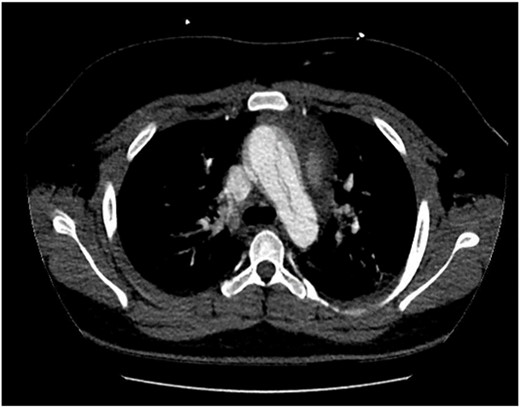

The patient was hemodynamically stable during his admission; however, worsening pain profile led to a serial electrocardiogram showing sinus rhythm with ST segment changes consistent with ischemia. There was an initial troponin rise of 245 ng/L progressing to a peak of 922 ng/L. The remaining blood panel was unremarkable. Chest X-ray showed no widened mediastinum and clear lung fields. A bedside transthoracic echocardiogram demonstrated a dissection flap with severe aortic regurgitation in the ascending aorta. Computed tomography aortogram was consistent with a Stanford Type A aortic dissection extending from the aortic root to the bifurcation of the common iliac arteries (Figs 1 and 2). There was involvement of the right brachiocephalic artery and right common iliac.

Computed tomography aortogram Axial Image of Stanford Type-A Aortic Dissection extending into arch and descending thoracic aorta.